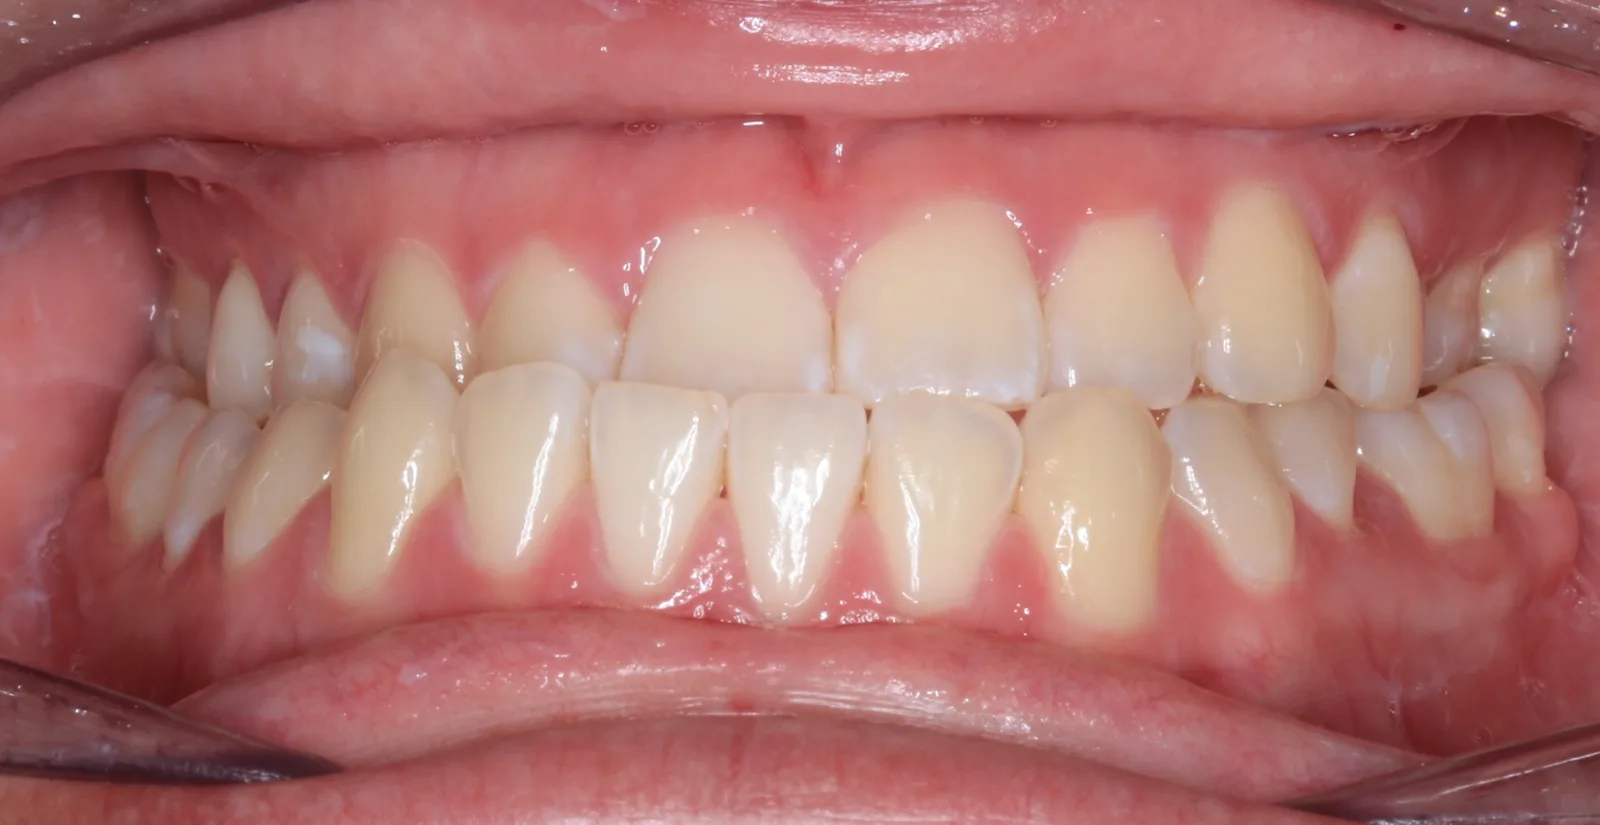

After teeth alignment comparison: Intraoral after photo of Metal Self-Ligating Braces & Orthognathic Surgery showing this transformation was designed with intention. After

This case began with a severe skeletal imbalance that braces alone could not correct. The patient presented with a significant Class III bite, asymmetric mandibular prognathism, anterior crossbite, and midline deviation. Because the jaw relationship was the root of the problem, a combined orthodontic and surgical approach was required to achieve the best stable, long-term result.

This transformation was designed with intention. Dr. Benson used braces to sculpt alignment and prepare the bite, then collaborated with an oral surgeon to reposition the mandible through orthognathic surgery. The result: a stable bite, restored facial balance, and symmetry achieved.